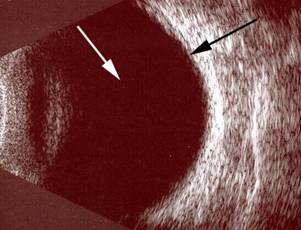

Resim 2: Yandaki resimde, vitreus içi kanaması olan bir hastanın retina fotoğrafı izlenmektedir. Resim 1’dekinin aksine buradaki görüntünün net olmadığı, göz siniri ve damarlarının net olarak seçilemediğini görmek mümkündür.